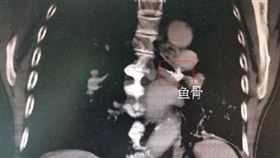

咳嗽2年多以為肺癌!醫揪元凶:火鍋害的

身體若有反常,千萬不要拖,趕緊就醫檢查比較保險。中國...